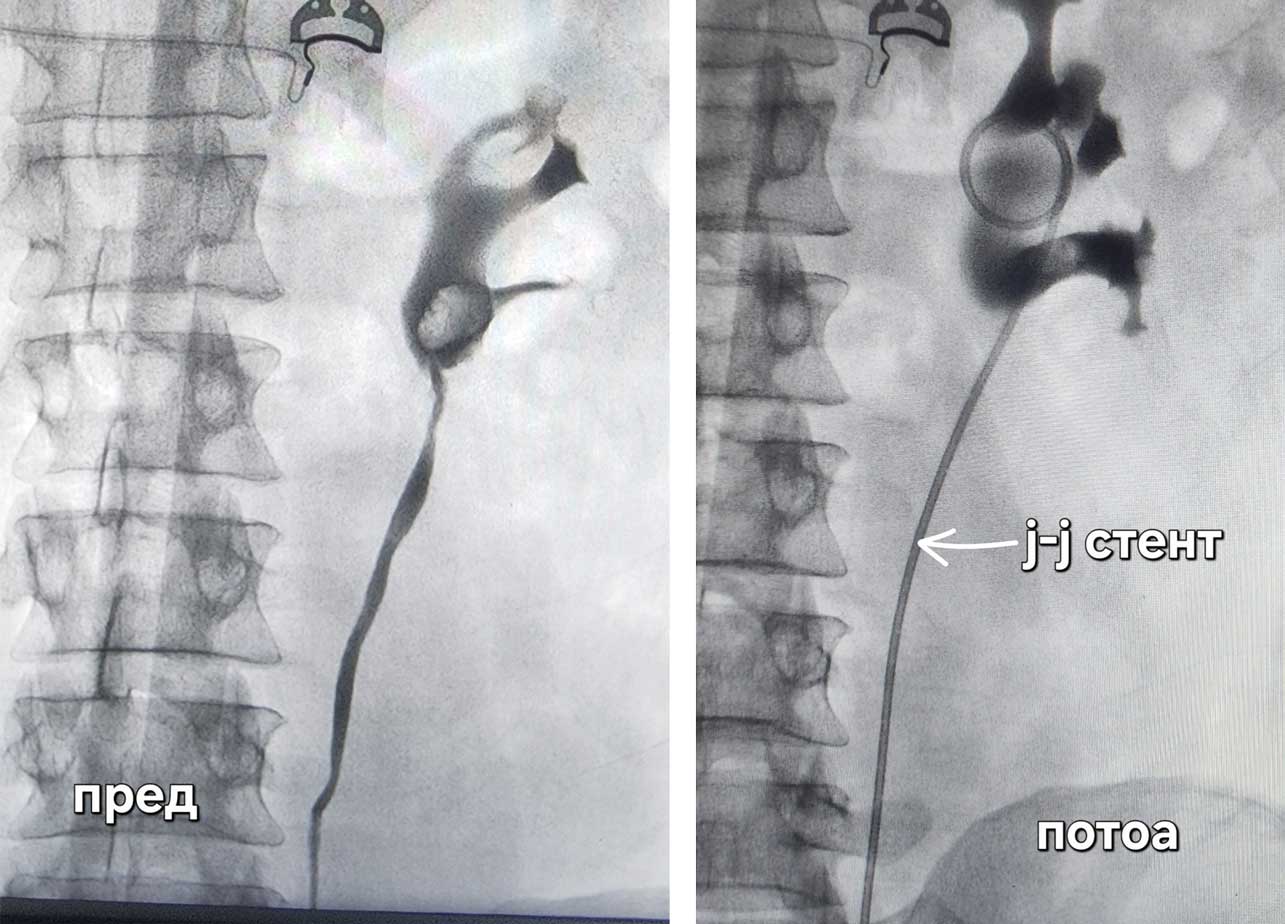

Во минатото оваа состојба секогаш се третирала со отворена хирургија, но по воведувањето на ендоскопските техники, третманот се врши преку природните отвори. Се мести т.н. џеј-џеј стент (J-J stent), односно цевче кое води од бубрегот до мочниот меур и има за цел да го празни блокираниот бубрег. Оваа метода која вклучува вградување на ваков стент во нашата болница се применува без пациентот да почуствува болка.

Во краткотрајна интравенска анестезија пациентот заспива и не чуствува ништо. Со цистоскоп се навлегува преку природните патишта. Откако ке се најдат отворите на уретерите (мочоводите од бубрегот до мочниот меур) се инстилира контраст во нив, при тоа со рентген се прават слики со цел да се визуелизира цел уретер. Со оваа снимка доста често можат да се видат и причинителите кои го затнуваат бубрегот.

Потоа се поставува хидрофилна жица, односно жица тенка колку влакно од коса за да може да ги надмине сите опструкции по патот, а воедно да не направи повреда по самите мочни патишта. Потоа по патот на жицата се поставува џеј-џеј стентот. Зафатот трае меѓу 30 минути и 1 час. По завршената интервенција пациентот си заминува дома.